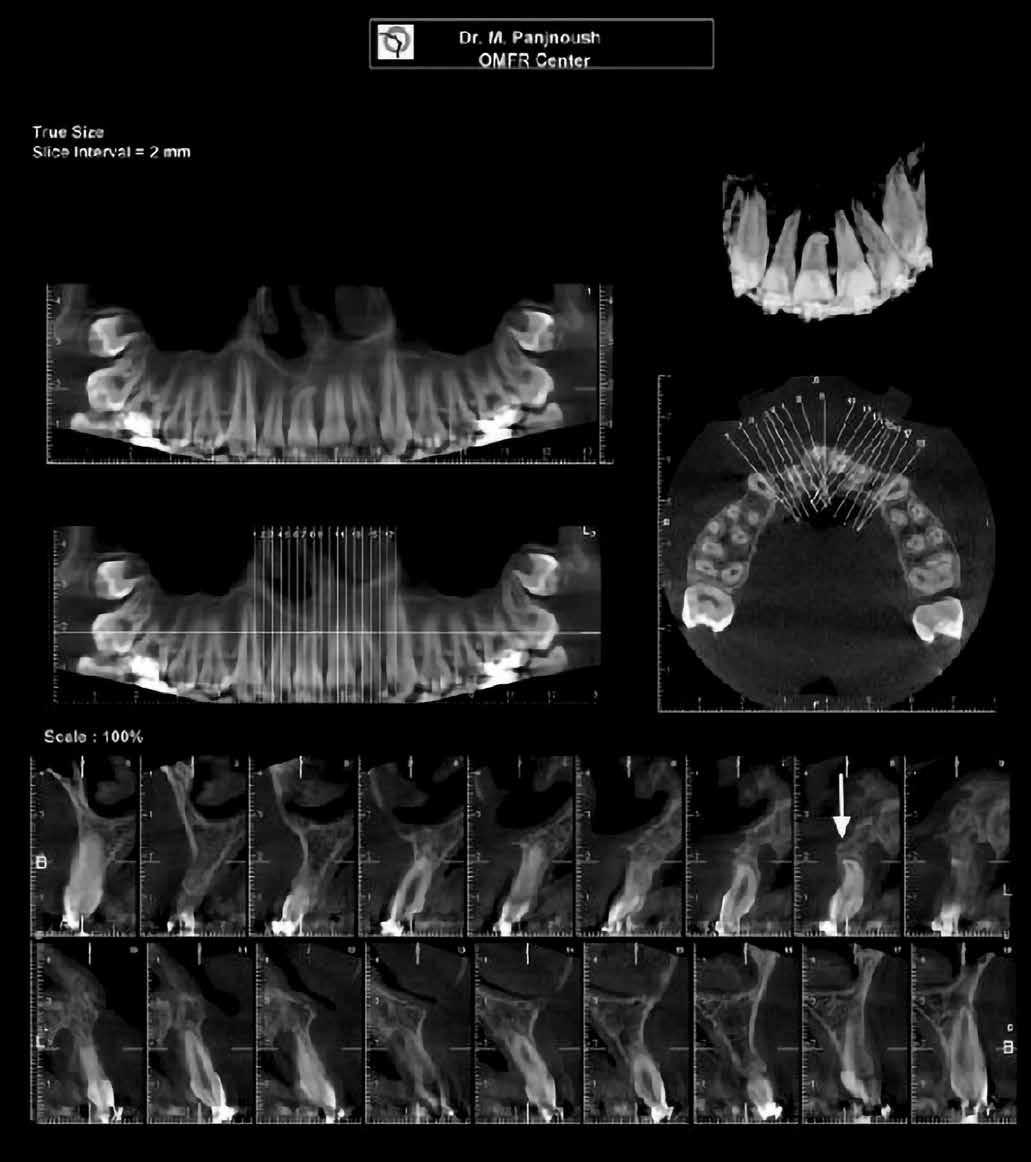

A 10 éves férfi páciens a felső frontfogai késői/nem megvalósuló előtörése miatt kereste fel a rendelőnket. A klinikai és a radiológiai vizsgálat során a jobb felső nagymetszőfog impakcióját észleltük (1. ábra). A fog horizontális tengelyállással és dilacerált gyökérrel rendelkezett. A felső dentális középvonal a fogak vándorlása miatt jelentős mértékben elcsúszott. A bal felső kismetszőfog is rendkívül kedvezőtlen pozícióba került.

Dr. Kazem Dalaie, dr. Samin Ghaffari, dr. Mazir Mir (Irán, Németország) 1. a ábra: Az intraorális felvételen jól látható a jobb felső nagymetszőfog lehetséges impakciójára utaló foghiány.

1. b ábra: A panoráma röntgenfelvételen megfigyelhető a teljes impakcióban lévő jobb felső nagymetszőfog. 1. c ábra: A CBCT felvétel is igazolja a jobb felső nagymetszőfog impakcióját.

4. a ábra: A CBCT felvétel igazolja, hogy a jobb felső nagymetszőfog megfelelő pozícióba került. Az ínyszél lefutása kedvező, a fog gyökere körül elfogadható mennyiségű csontállomány ábrázolódik, valamint a gyökérfelszívódás mértéke sem túl kifejezett.

6 hónapon keresztül tartott. Ennek megfelelően a fog körül található szövetek a felszabadítás, valamint a havi kontrollok során 975 nm-es (több mint 25 J/cm2 energiasűrűség) és 660 nm-es hullámhosszúságú (12–18 J/cm2 energiasűrűség) lézersugarakkal is megvilágításra kerültek. Az impaktálódott fogat megközelítőleg 7 hónap alatt tudtuk megfelelő pozícióba mozgatni (3. ábra). Az orthodoncia kezelés aktív szakasza 18 hónapon keresztül tartott. A fogívek végső nivellálását és a fogak végleges pozícióba rendezését 0.018 × 0.025-ös acélívekkel végeztük.

A kezelés befejezésekor a páciens mosolya drámai mértékben javult, továbbá a frontfogak elhelyezkedése és az ínyszél lefutása is szemmel látható módon kedvezőbbé vált (4. ábra). A kezelés végén készült CBCT felvétel nem mutatta

csontfelszívódás jelenlétét, és csupán minimális mértékű gyökérfelszívódás bekövetkezését igazolta.

4. b ábra: A panoráma röntgenfelvétel is alátámasztja a CBCT felvételen látottakat. 4. c ábra: Az intraorális felvételen megfelelő fogpozíciók és kedvező ínyszéli lefutás ábrázolódik.